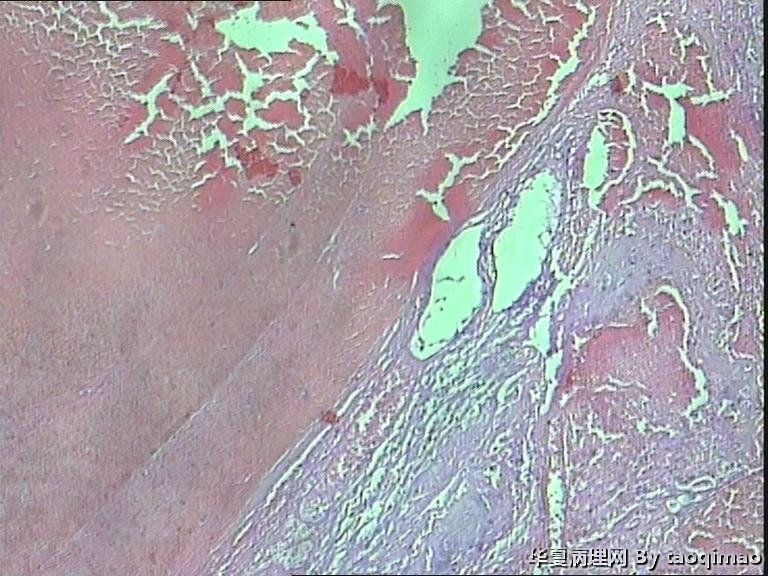

功血,滋养细胞浅肌层?

这是患者第一次刮宫的内膜,怎么出报告呢

上一组图是全子宫切除后宫内膜及浅肌层的切片,取材时发现在子底及后壁有暗紫色血凝块与宫内膜分界不清

患者资料:39岁女,阴道不规则出血,2011,6,诊刮可见:内膜腺体囊性增生,现再次出血诊刮术。术中子宫后位,宫深9cm,子宫增大内膜不平,刮出内膜组织约2g。红褐色破碎组织一堆大小3X2.5cm,质软。